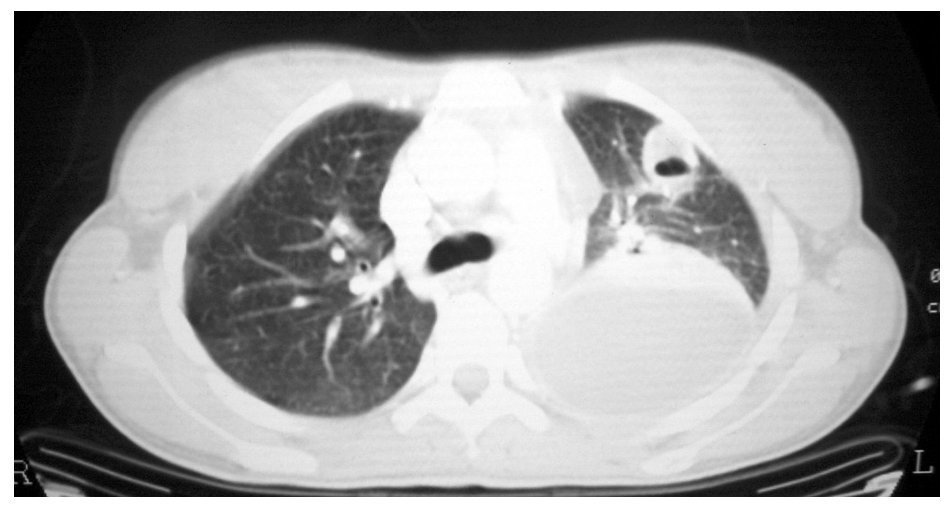

Fig. 2. Tomografía computarizada de tórax.

Se realizaron pruebas de imagen consistentes en radiografía simple de tórax y senos paranasales, tomografía computarizada de tórax, ecografía abdominal y ecografía doppler cervical.